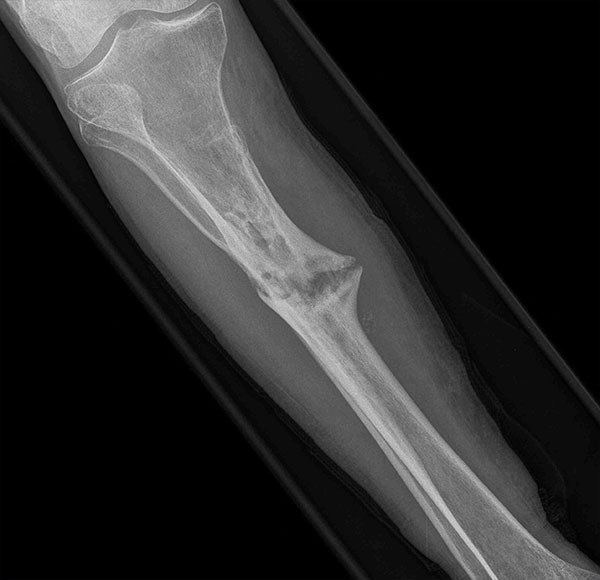

- Focus Area Management of Pain & Psychosocial Sequelae

- Sponsor DoD PRORP

- Primary Objective Evaluate the effect of standard pain management without NSAIDs (Group 1) vs. standard pain management plus up to 6 weeks of NSAIDs (Group 2) in the treatment of tibial shaft fractures.

- Ongoing